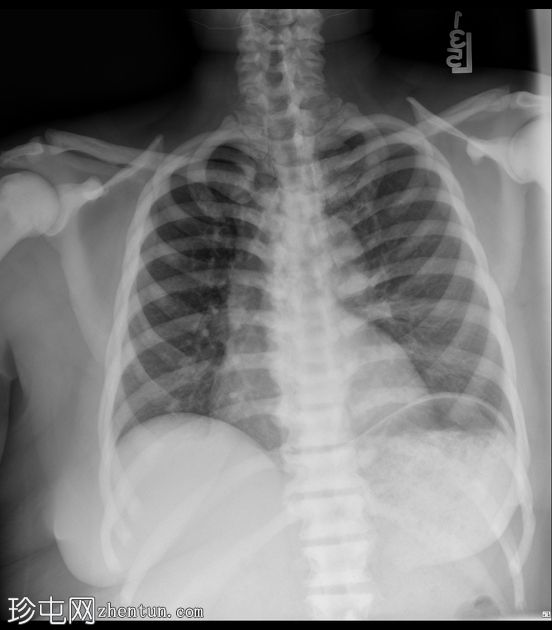

X线片

正位

侧位

弥漫性骨硬化,符合骨硬化症病史。无水肿或

肺

炎。

心脏

轮廓增大。